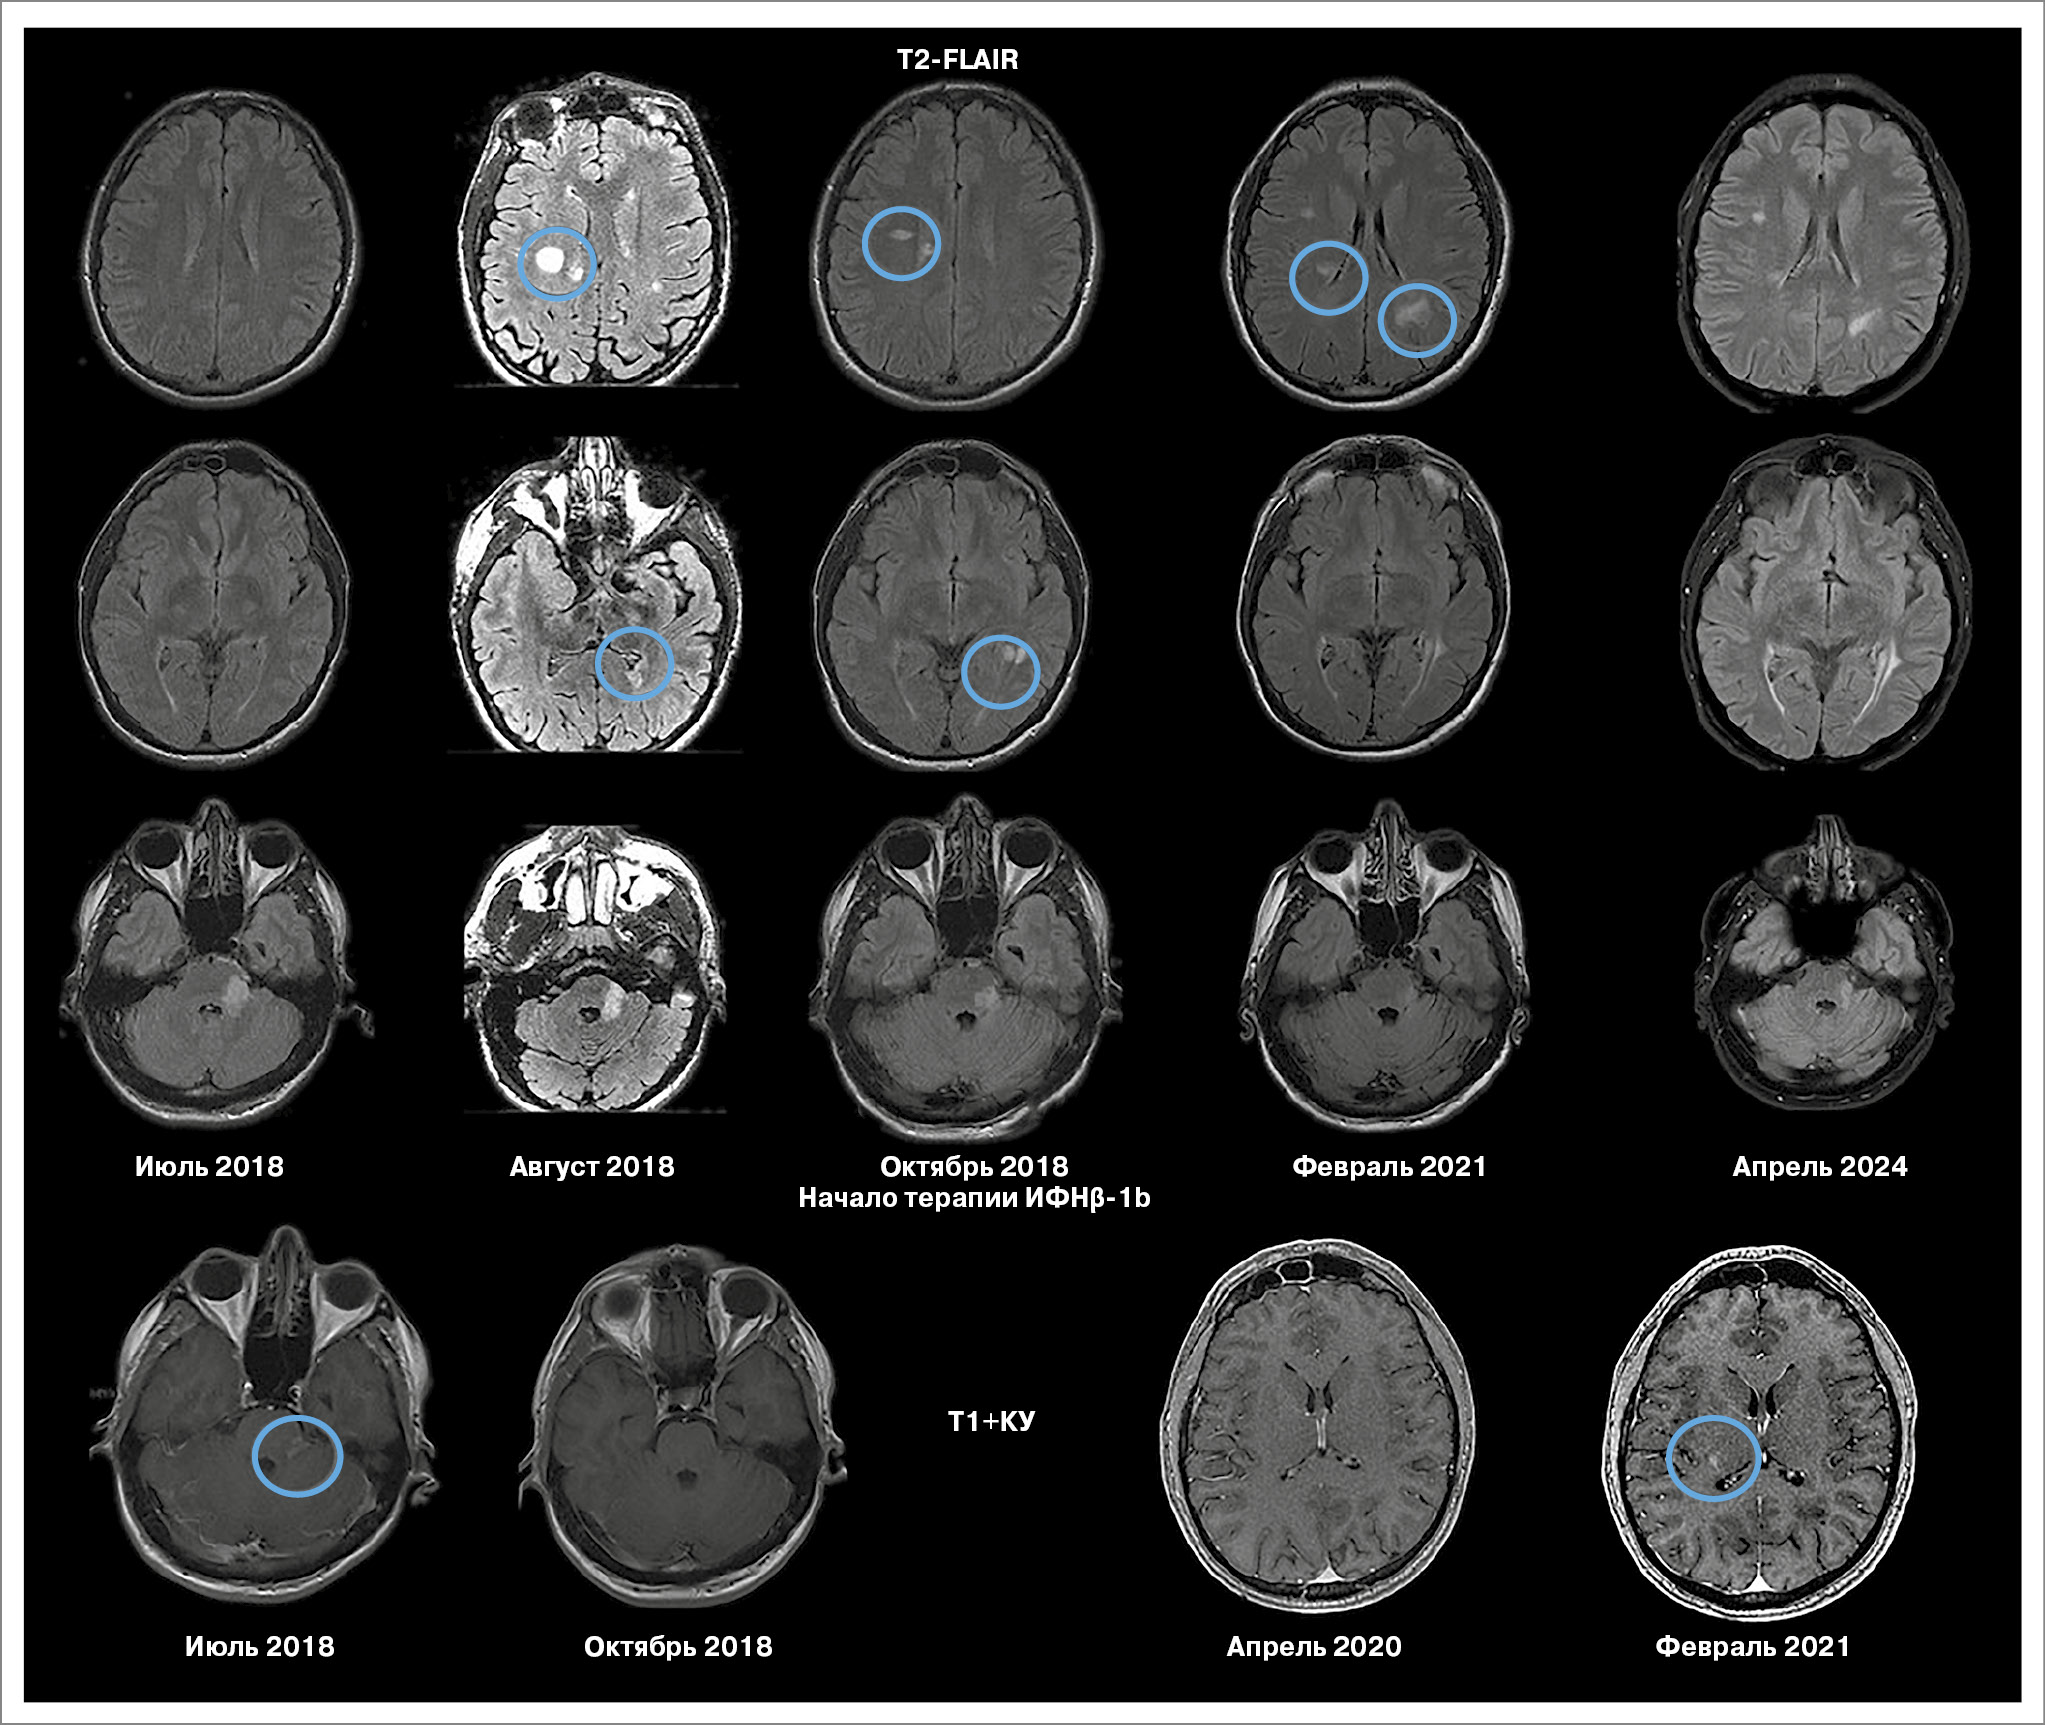

Пациент Ш., мужчина, 1990 г.р. Дебют заболевания в июле 2018 г. (возраст 28 лет), когда резко возникло головокружение системного характера, шаткость при ходьбе, подобный эпизод повторился на следующий день. Через несколько дней появилось онемение правой половины тела. По данным МРТ головного мозга выявлено образование в левой средней ножке мозжечка, левой половине моста, частично накапливало контрастное вещество, подозрение на глиому левой средней ножки мозжечка. Консультирован в ФГАУ «НМИЦ нейрохирургии им. акад. Н.Н. Бурденко» и ГБУЗ «НИИ СП им. Н.В. Склифосовского». При выполнении МРТ головного мозга в динамике через 1 мес выявлены 2 новых очага в мозолистом теле и перивентрикулярно (рис. 2). По данным МР-спектроскопии убедительных данных за наличие опухолевого процесса не получено. Присоединились жалобы на дискоординацию в правых руке и ноге.

Рис. 2. МРТ пациента Ш. (клинический случай 2).

Выполнено исследование сыворотки и ликвора на олигоклональные антитела, тип синтеза 2. Поставлен диагноз «РС, ремиттирующее течение, псевдотуморозная форма».

Проведена пульс-терапия метилпреднизолоном в курсовой дозе 6 г с положительным эффектом, зарегистрировано снижение балла EDSS до 2,0. Назначен ПИТРС ИФНβ-1b (Инфибета®, АО «Генериум») 9,6 млн МЕ подкожно через день. В первые 2 мес пациент отмечал частое развитие гриппоподобного синдрома с повышением температуры до 39,2°С, слабостью, мышечной и суставной болью, периодическим онемением в правой ноге. В дальнейшем данные нежелательные реакции не наблюдались. На фоне 6-летней терапии клинических обострений не зарегистрировано. С середины декабря 2020 по январь 2021 г. в связи с задержками поставок препарата был вынужденный перерыв в лечении. Возобновление применения препарата осуществлялось с титрацией дозы. По данным МРТ головного мозга (февраль 2021 г.): отрицательная динамика в виде появления очага на границе таламуса и задних отделов наружной капсулы, накапливающего контраст (см. рис. 2). При повторных исследованиях до 2024 г. радиологическая активность отсутствует, EDSS остается стабильным – 1,5 балла.